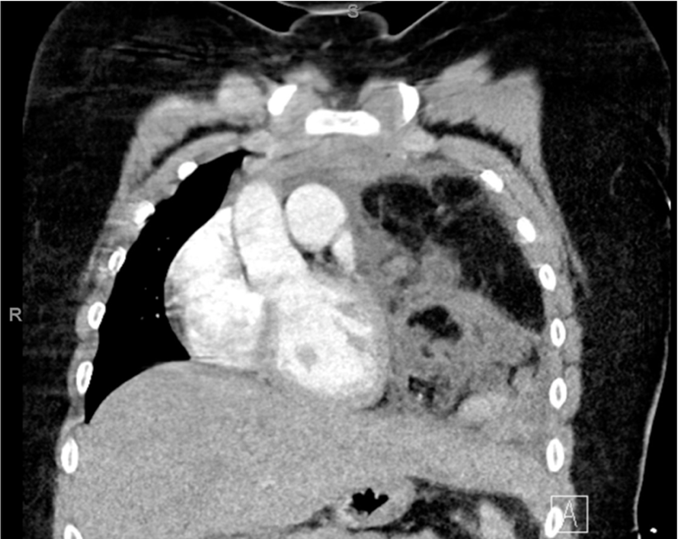

📖 #RadExam Study Guide 📖

A 13 yo male presents with chest pain. CXR shows near-complete opacification of the left hemithorax with rightward mediastinal shift. Most likely diagnosis from chest CT?

A) Necrotizing pneumonia

B) Teratoma

C) Lymphoma

D) Diaphragmatic hernia